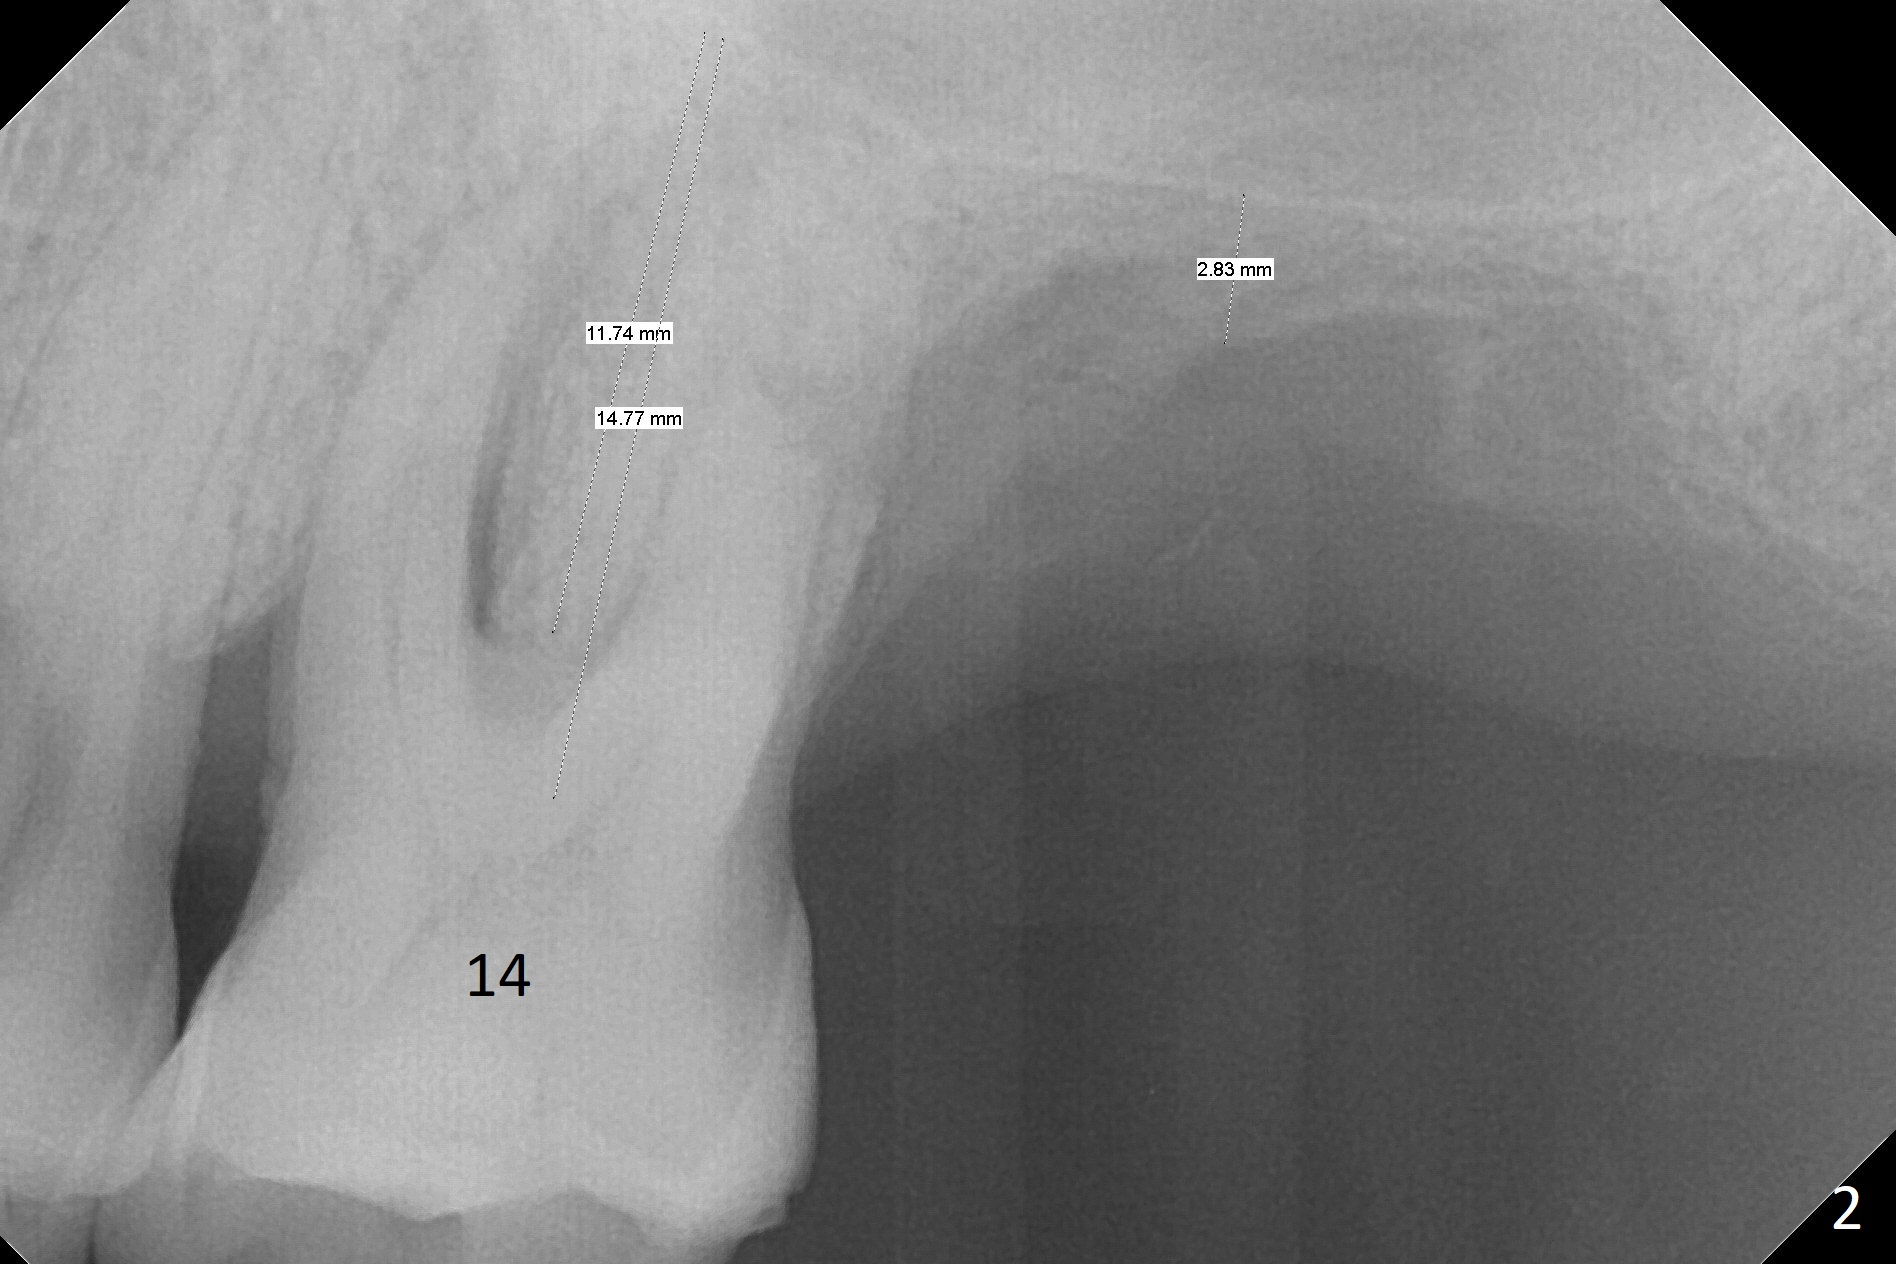

A 64-year-old man has poor dentition (Fig.1 (taken a year ago)). After extraction of #15 and 17 in China, the tooth #14 develops retrograde pulpitis with severe buccopalatal gingival recession (Fig.2). It appears that the septum is longer than the buccopalatal plates. A small and relatively long implant (3.8 or 4x11.5 mm) is placed within the boundary of the septum. The most peripheral socket is packed with PRF membranes (2-3 tubes) and collagen plug, while the portion close to the implant threads with Vera Graft. Please remember osteotomy depths with hard and soft tissue landmarks (Fig.2).